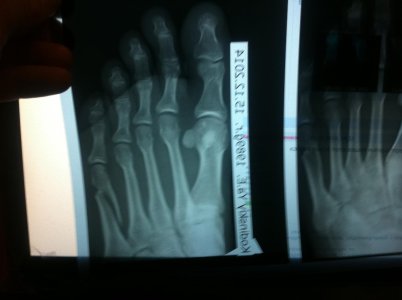

Получил перелом 5 плюсневой кости со смещением.

Ноложили временно гипс и мой доктор говорит что нужно хирургическое вмешательство

Такой вопрос: Нужно ли хирургическое вмешательство и какие могут быть последствия

без хирургического вмешательства

Фото прилагаю

IMG_3331.jpgIMG_3332.jpg

Трудно на основании скудной информации делать заключение. Возраст, как я понял молодой, перелому 5 дней. Формально можно без операции, срастется без последствий (стельки не забудьте после снятия гипса)